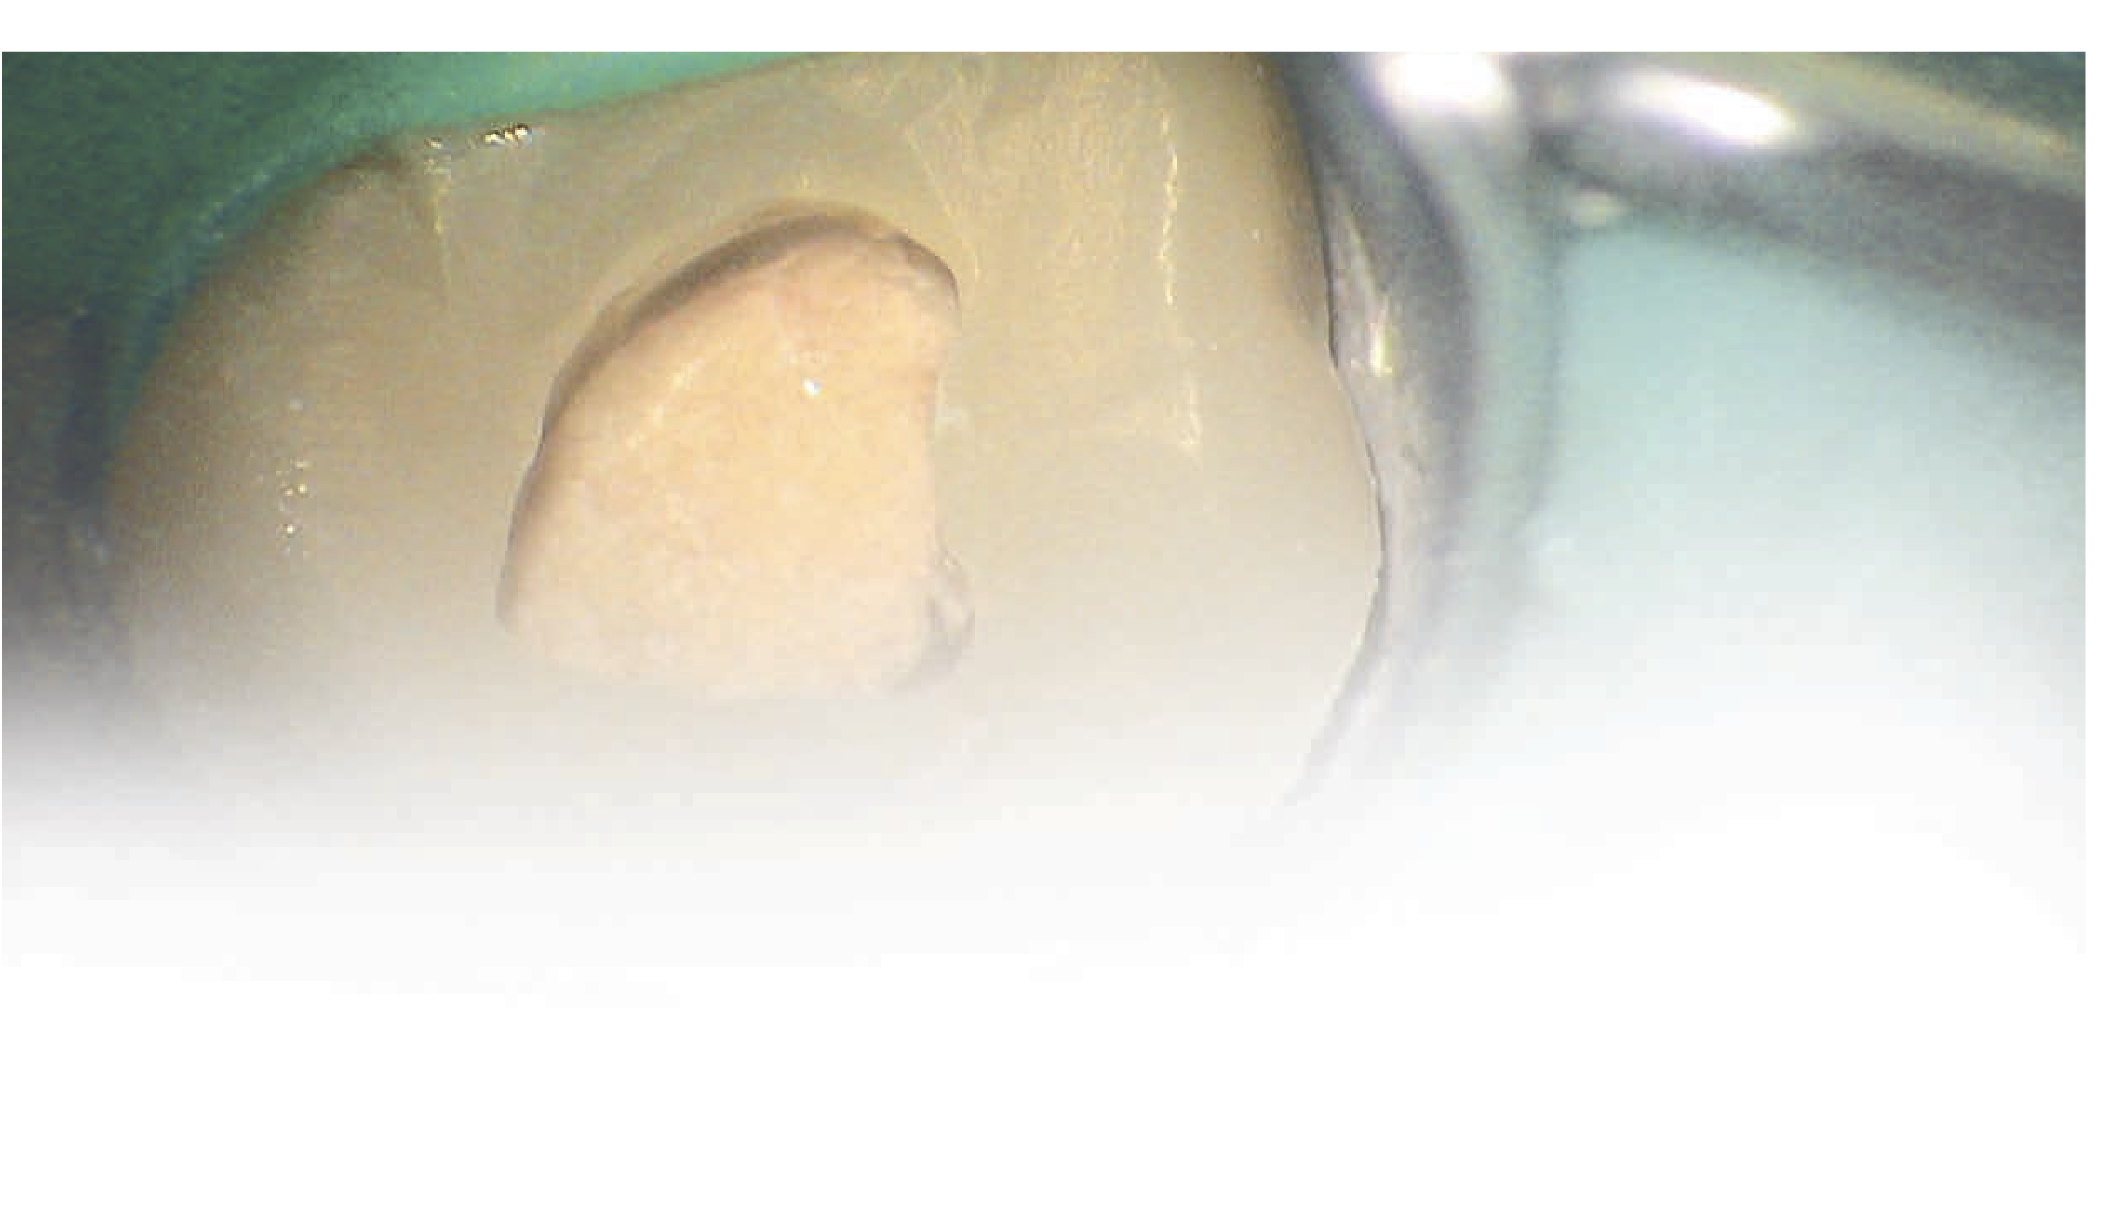

Для ирригации использовали 3% р-р NaOCl, 17% ЭДТК и пассивную ультразвуковую ирригацию (ПУИ) Irrisafe. Пломбирование осуществляли с помощью силера Kerr RC GP SystemB и Obtura. Было обнаружено, что дно пульповой камеры имело ненормальный сотообразный вид. Отверстие для доступа восстановили с помощью СИЦ. Спустя четыре месяца после лечения зуб стал чувствительным к перкуссии (ЧКП). Десна со стороны щеки и неба были воспаленными и мягкими, а вероятная фуркация составляла до 5 мм.

Зуб изолировали с помощью коффердама; отверстие для доступа открыли повторно, после чего удалось рассмотреть обширное повреждение дна пульповой камеры, которое легко кровоточило.